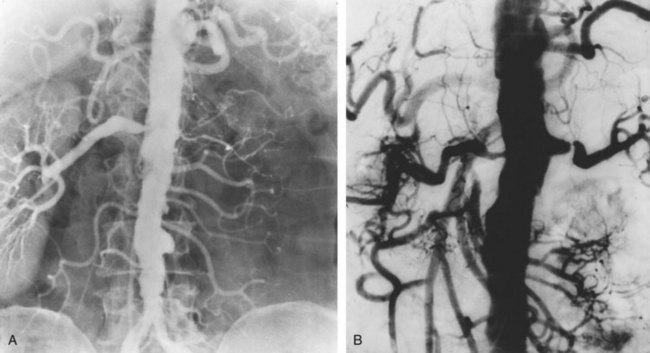

The arteriogram in perimedial fibroplasia may give the appearance of arterial beading, but careful observation shows that the caliber of the normal segment of the vessel is not exceeded by the “bead” (Fig. 39–6). This fact, along with the frequent occurrence of extensive collateral circulation, differentiates this lesion angiographically from that of medial fibroplasia. Perimedial fibroplasia produces severe stenosis, and, although complicating thrombosis or dissection is relatively uncommon, progressive obstruction with ischemic renal atrophy occurs in almost all patients managed nonoperatively.

Figure 39–6 Renal arteriogram in a patient with perimedial fibroplasia shows slightly irregular, yet severe, stenosis of the midrenal artery (arrows) associated with extensive collateral circulation to the kidney. The small size of the arterial irregularities and the presence of collateral circulation distinguishes this lesion radiographically from medial fibroplasia.

(From Novick AC. Renal vascular hypertension in children. In: Kelalis PP, King LR, Belman AB, editors. Clinical pediatric urology. Philadelphia: WB Saunders; 1984.)